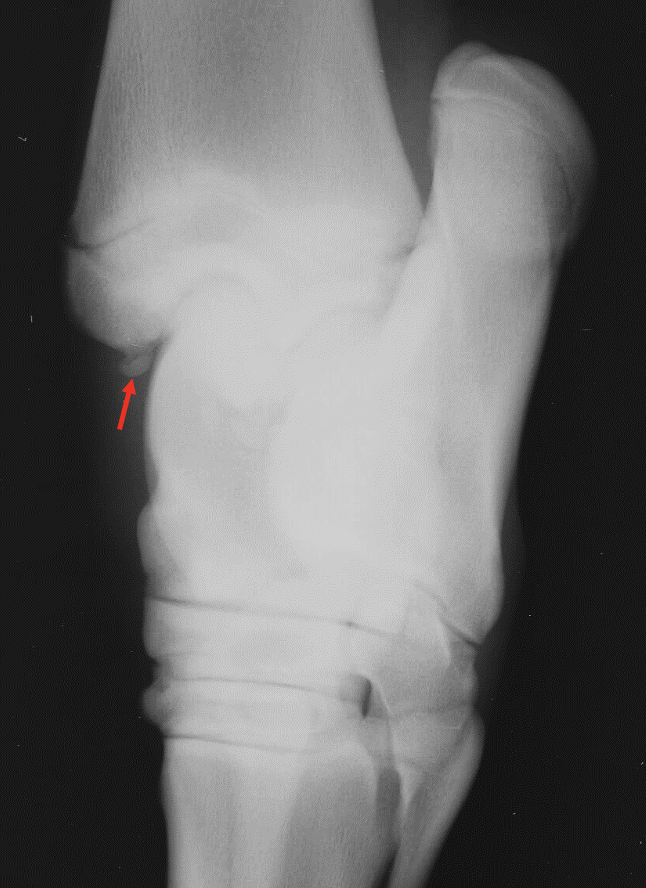

What is shown in these images?

A

osteochondrosis/OCD at intermediate ridge of tibia (DIRT)

-visible fragment